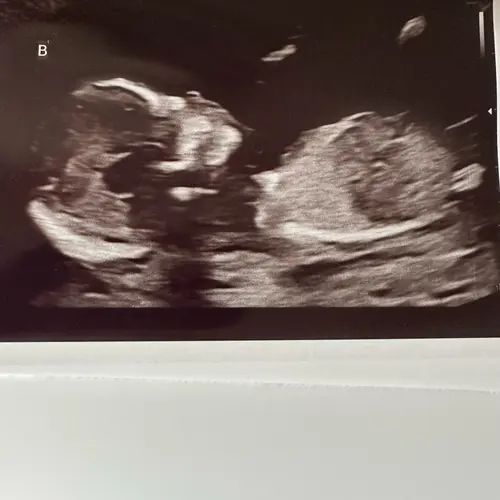

Ik heb alleen deze nog maar denk dat deze ook niet duidelijk genoeg is

Hmmm twijfel hoor.. denk een jongen

Ik heb hier een betere foto..

Denk jongetje